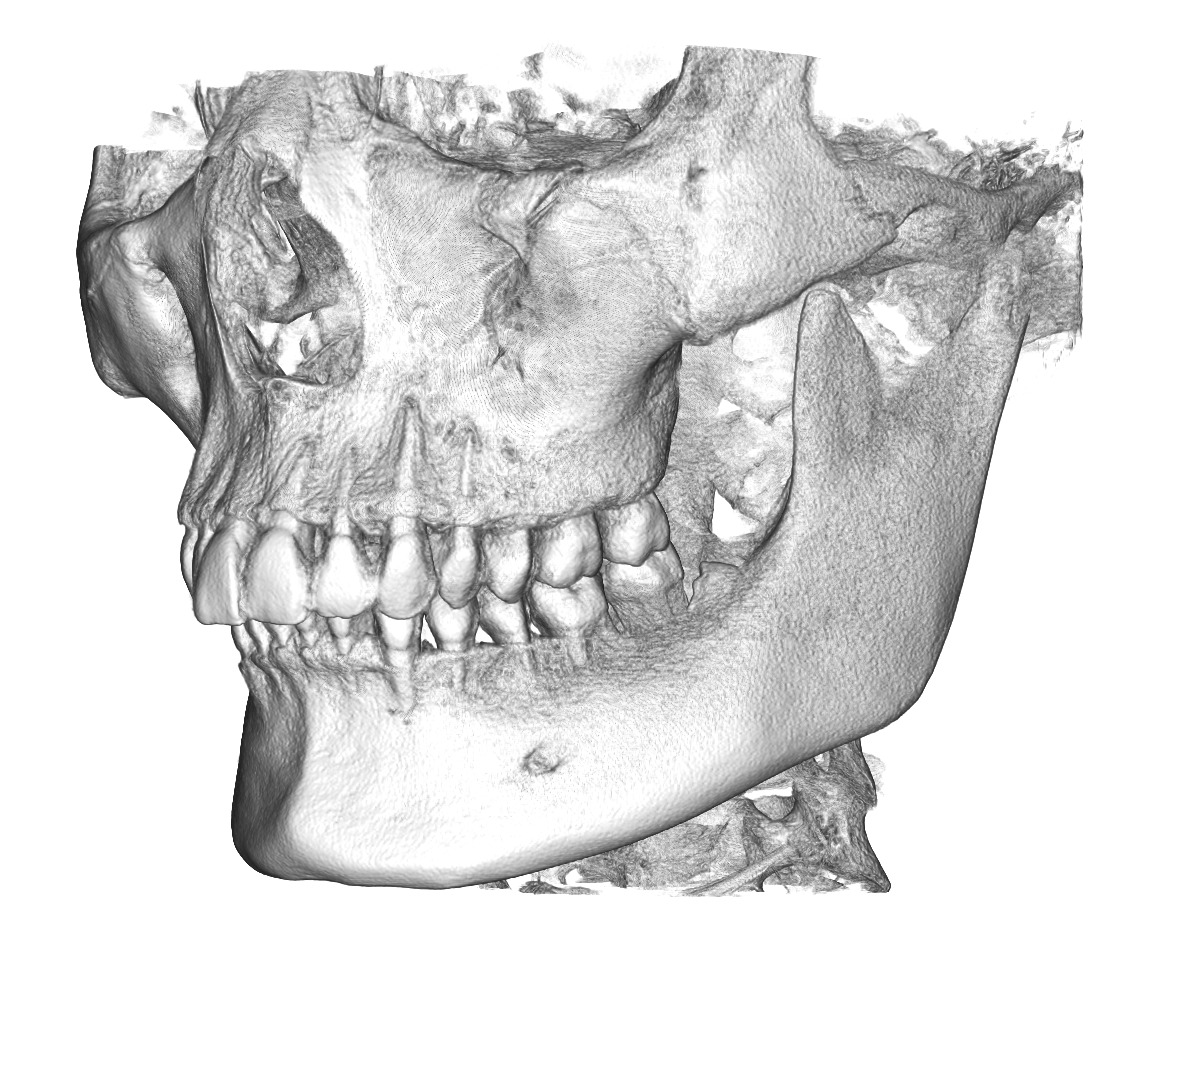

Split into parts

13